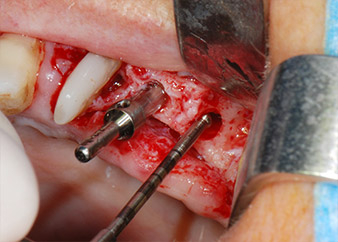

Un mese più tardi, nel giorno programmato per l'intervento, il dolore e l'infiammazione in corrispondenza del dente 24 erano minimi, ma era ancora presente mobilità di classe 2 secondo Miller. Dopo l'apertura dei lembi e la pulizia del tessuto periapicale e periradicolare infetto, l'estensione della mancanza ossea si è resa evidente (Figg. 2 e 3).

Tutto il tessuto osseo vestibolare e distale era mancante in corrispondenza della radice buccale. La possibilità di attacco era essenzialmente ristretta alla radice palatale, evidenziando la prognosi negativa preliminare. Anche il dente 27 mostrava un punto di attacco orizzontale ridotto e una rarefazione apicale minima (cfr. Fig. 1), senza sintomi clinici.

perdita totale di tessuto osseo e attacco

Fig. 2 e 3: Dopo aver sollevato i lembi, un mese dopo il pretrattamento endodontico e l'inizio della terapia periodontale sull'intera dentatura, la radice buccale del dente 24 mostrava una perdita totale di tessuto osseo e di punti di attacco.